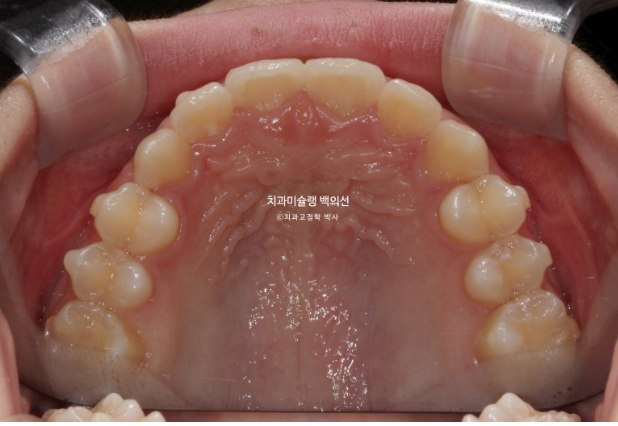

25.04

중심선은 정확하게 맞으며 과개교합이 잘 해소되었습니다.

어금니 교합은 물샐틈 없는 1급입니다.

유지장치까지 들어간 모습입니다.

총 치료기간은 1년 2개월, 재제작은 1회 했습니다.